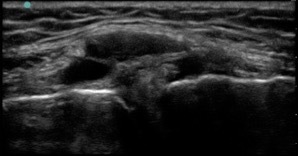

Knee Meniscus Complex Cyst Image